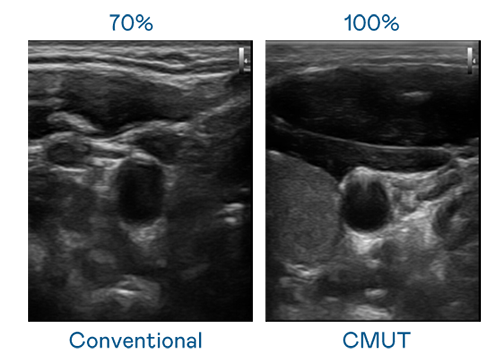

CMUT 技术是一种用电容式微机电元件来产生超音波讯号的技术。与传统 PZT 压电式技术相比,CMUT 频宽增加 30%,更宽频的超音波讯号让影像解析度大幅提升,是实现高影像品质医疗超音波扫描、促进精准医疗发展的关键技术。

超音波影像的解析度高低,首先取决于探头能发出的讯号频宽。尊龙凯龙时官网进入 CMUT 可提供高清晰的超音波讯号,提供高频宽、高灵敏度、影像纹理细节更高的超音波影像,协助医护人员缩短影像判读时间及利用精准的医疗影像进行诊断。